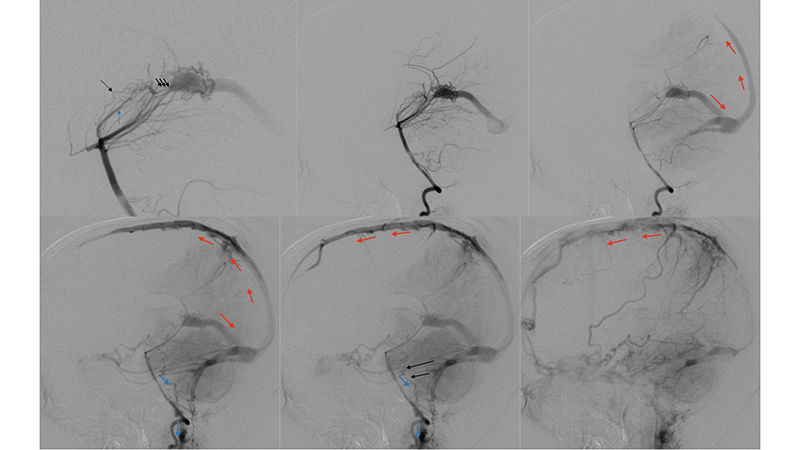

- Πλαγία λήψη κατά την έγχυση στην δεξιά έσω καρωτίδα. Υπάρχει εξεσημασμένη φλεβική συμφόρηση του άνω οβελιαίου κόλπου, προς το σύστημα της φλέβας του Troland (μπλέ βέλος), τον σηραγγώδη κόλπο και τό έδαφος του προσθίου κρανιακού βόθρου (μαύρα βέλη) και το πτερυγοειδές πλέγμα.

- Πλαγία λήψη κατά την έγχυση στην αριστερή έσω καρωτίδα. Η φλεβική παροχέτευση της αρτηριοφλεβώδους επικοινωνίας προς το σύστημα του άνω οβελιαίου κόλπου (κόκκινα βέλη) με εξεσημασμένη φλεβική συμφόρηση και κινητοποίηση παράπλευρων διαμυελικών φλεβών προς το σύστημα της επιπολής μέσης εγκεφαλικής φλεβός (μπλέ βέλος) και διά του σφηνοβρεγματικού κόλπου προς τον σηραγγώδη κόλπο ενώ το εν τω βάθει φλεβικό δίκτυο αποχετεύεται μέσω των αναστομώσεων με το σύστημα της εν τω βάθει μέσης εγκεφαλικής φλεβός (διακεκομμένο μπλέ βέλος) προς το σύστημα επίσης του σηραγγώδους κόλπου.

- Πλαγία λήψη κατά την έγχυση στην αριστερή σπονδυλική αρτηρία. Τροφοφόροι θαλαμοδιατιτραίνοντες (διακεκομμένο μαύρο βέλος) και υποεπενδυματικοί κλάδοι (διακεκομμένο μπλέ βέλος), εκ της οπισθίας αναστομωτικής και του Ρ1 τμήματος των οπισθίων εγκεφαλικών αρτηριών, που πορευόμενοι στο πλάγιο τοίχωμα της 3ης κοιλίας εκατέρωθεν, συναντούν την χοριοειδή σχισμή και εκείθεν αρδεύουν την αρτηριοφλεβώδη επικοινωνία (μαύρα βέλη). Παρατηρείται αναστροφή της ροής στον άνω οβελιαίο κόλπο με φλοιώδη παλινδρόμηση προς τα εγκεφαλικά ημισφαίρια αμφοτερόπλευρα (κόκκινα βέλη). Οι εγκάρσιοι κόλποι αποφράσσονται, και μέσω των περιμεσεγκεφαλικών φλεβών παρατηρείται παροχέτευση προς το περιμυελικό φλεβικό δίκτυο του νωτιαίου μυελού (μπλέ βέλη) το οποίο παρουσιάζει εκσεσημασμένη συμφόρηση αλλά και διά του άνω λιθοειδούς κόλπου προς τον σηραγγώδη κόλπο (μαύρα βέλη).

- Αξονική τομογραφία με σκιαγραφικό και αγγειογραφία του σπονδυλοβασικού συστήματος σε πλάγια λήψη. Διακρίνεται κατιούσα φλεβική παροχέτευση προς το περιμυελικό φλεβικό δίκτυο του νωτιαίου μυελού (μπλέ βέλη) το οποίο παρουσιάζει εκσεσημασμένη συμφόρηση.